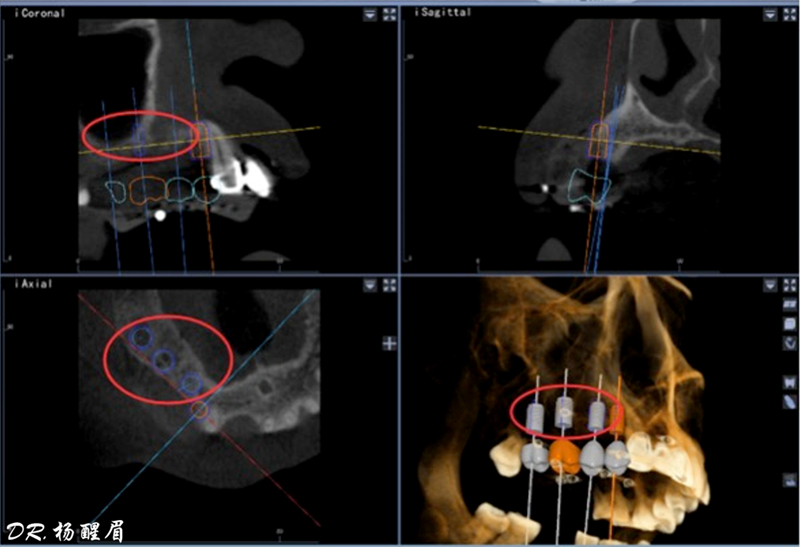

此病例中主刀醫(yī)生借助迪凱爾數(shù)字化口腔種植手術(shù)導(dǎo)航系統(tǒng),精確的控制每鉆的定點(diǎn)精度和角度,保證了每次制備定點(diǎn)誤差小于0.4mm,角度偏差不大于3.5°,極大的保證了種植體按照種植前的手術(shù)設(shè)計(jì)就位。